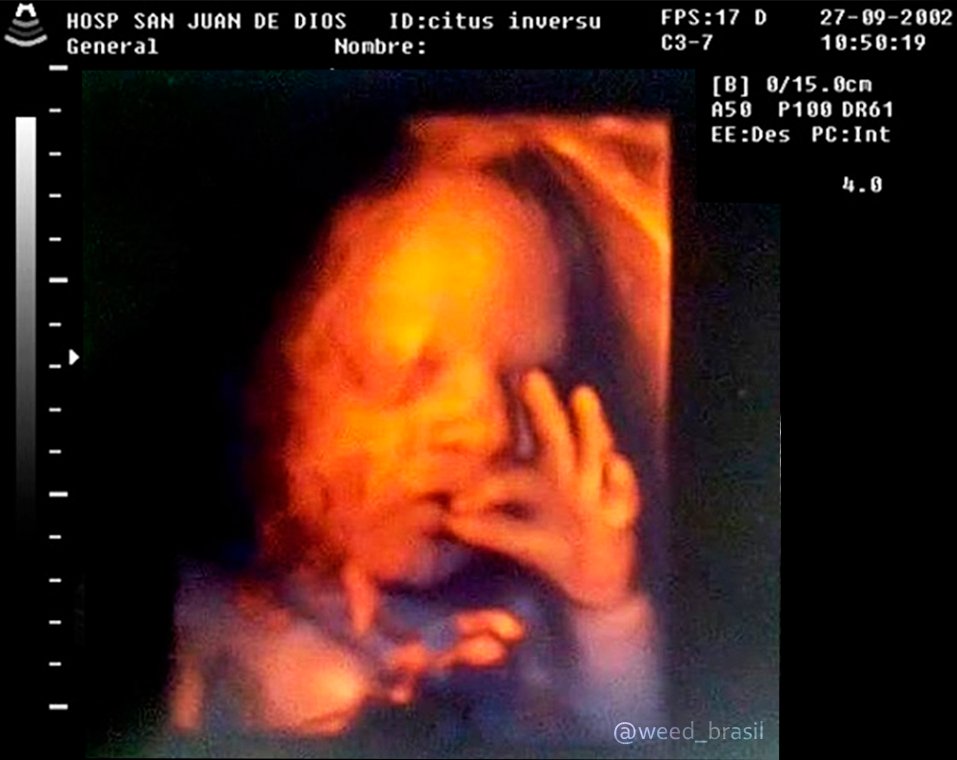

Ultrassom 3d